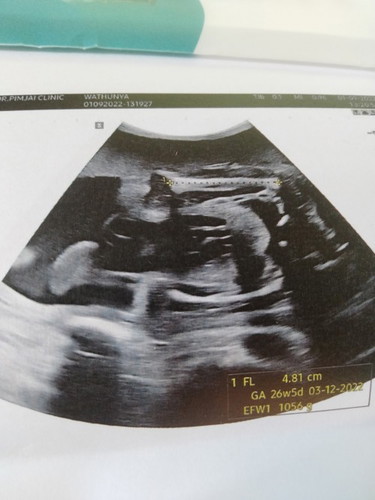

27 week ช่วยลุ้นเพศหน่อยค่ะ

ชาย หรือ หญิง คะ

น่าจะหญิงมั้งคะ เดาๆ555